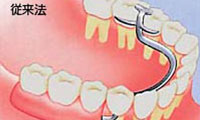

失った部位の両隣の健康な歯を削ってブリッジにして固定します。

失った部位だけにインプラントを埋めますので、健康な歯を傷つけません。

健康な歯に金属のバネをかけて入れ歯を固定します。違和感があり、バネをかけた歯にも負担がかかります。

入れ歯の床や金具の違和感がなくバネをかけた健康な歯への負担もありません。